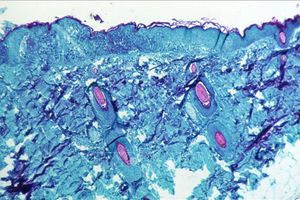

Old  Default Israel phát hiện thêm một ca bệnh đậu mùa khỉ

Theo phóng viên TTXVN tại Tel Aviv, Bộ Y tế Israel vừa thông báo đã phát hiện thêm một trường hợp nhiễm bệnh đậu mùa khỉ, là trường hợp thứ hai được phát hiện tại quốc gia này.

Bệnh nhân là một nam giới 30 tuổi, nhập viện với các triệu chứng ban đầu của bệnh đậu mùa khỉ. Các xét nghiệm sau sau đó tại Viện Nghiên cứu Sinh học Israel đã khẳng định điều này.

Trước đó, hôm 21/5 Israel cũng phát hiện ca nhiễm đậu mùa khỉ đầu tiên, là một công dân trở về từ châu Âu. Bộ Y tế Israel đang phối hợp với các cơ quan y tế nước ngoài và theo dõi chặt chẽ dịch bệnh ở trong nước.

Virus đậu mùa khỉ thường thấy ở động vật hoang dã, nhưng cũng lây lan sang người. Người bệnh thường xuất hiện phát ban trên tay, mặt giống bệnh thủy đậu, kèm theo các triệu chứng như sốt, nhức mỏi, nổi hạch, ớn lạnh, suy nhược cơ thể.